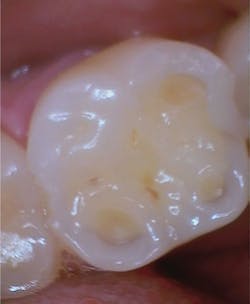

Reports of clinical characteristics similar to GERD destruction and disordered eating practices seem to be increasing. The teeth may appear dull, smooth, and increasingly thin. Over time, this may not even be noticeable to the patient. The whitewashed appearance that is found in disordered eating practices may not even be evident to a clinician in the early stages. Once seen, it is usually not forgotten.

Show the patient the areas of concern. Show the patient an image of a tooth with normal anatomy and compare it with the loss of anatomy in the patient’s teeth.